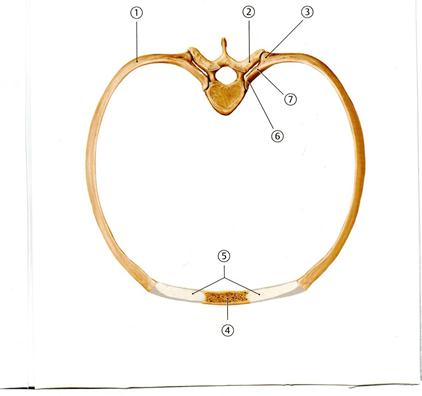

D. Бүйір массалар

D. Жартылай сыңар